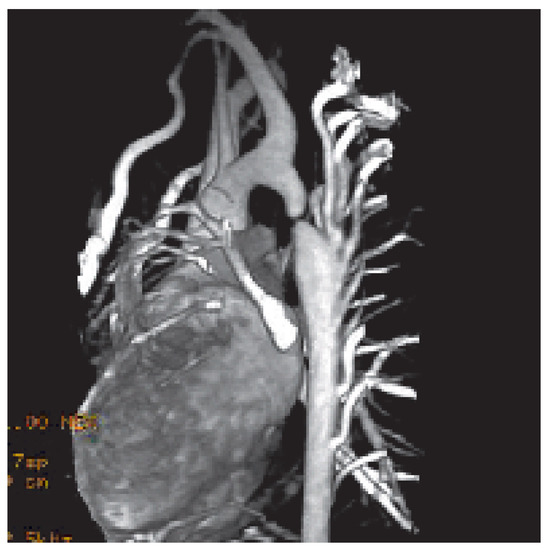

Fallbeschreibung. Ein 10jähriger Knabe wurde zur Abklärung eines Systolikums bei unauffälliger Anamnese und insbesondere uneingeschränkter körperlicher Belastbarkeit vorgestellt [...]